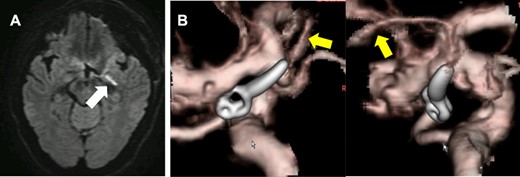

The patient was put under general anesthesia and MEP recordings were performed with needle electrodes for transcranial electrical stimulation placed on the scalp at the C3 and C4, according to the International 10-20 System. Stimulation (rate: 0.5 Hz, intensity: 70–90 mA, duration: 0.2 ms) was performed with train of six pulses with inter stimulus intervals of 2 ms. Compound muscle action potential was recorded from the bilateral abductor pollicis brevis and contralateral abductor hallucis, using a pair of needle electrodes. The patient was placed supine with the head rotated 15° to the right side fixed with a three-pin head frame. The surgery started with cervical dissection to secure the left common carotid artery and ICA for proximal control. The external carotid artery and superior thyroid artery were also dissected to enable retrograde suction decompression (RSD). Then, a curved skin incision was made following the previous surgical scar, and a frontotemporal craniotomy was performed. A distal Sylvian fissure dissection approach was performed to expose the carotid bifurcation, recurrent ICA–AchA aneurysm and the surgical clip. AchA’s main trunk was detached from the aneurysm dome while performing RSD, but two thin perforating branches were found arising from the aneurysmal dome (Fig. 2).

After Sylvian fissure dissection, the recurrent aneurysm (open white arrow) and the surgical clip (yellow arrow) were exposed. AchA’s main trunk (gray arrow) was detached from the aneurysm (compressed by microscissors), and the AchA main trunk was confirmed to arise from the ICA. Two small AchA branches were also found arising from the aneurysmal dome (white arrow). The two small AchA branches were temporarily occluded for 10 min.